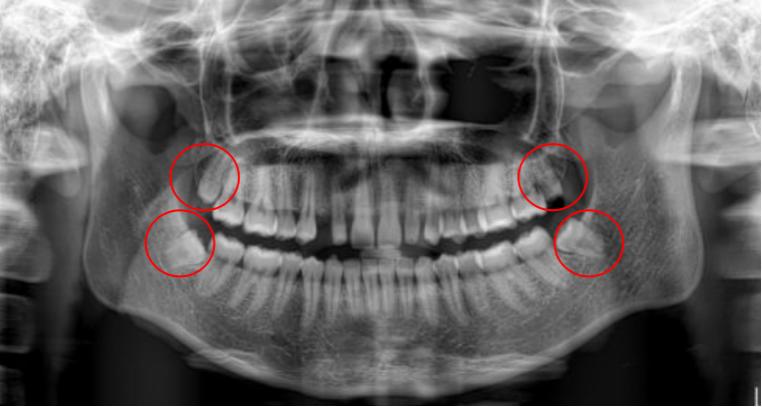

随着人类的进化,头面部的骨骼,肌肉,牙齿也在退化,只是骨头较牙齿退化得快一些。也就是骨头变小的速度大于牙齿数目减少的速度,导致相对较小的骨头容纳不下现在的牙齿,智齿又最后萌出,没有了空间,可能完全阻生,也可能部分或完全萌出。

萌出之初,牙冠和牙肉之间形成空隙。上颌因为智齿靠近软腭,刷牙易引起恶心,下颌智齿靠下颌骨的前方,空间有限,牙刷刷头较难深入,清洁不到位,食物残留,细菌聚集,引发感染,称智齿管周炎。